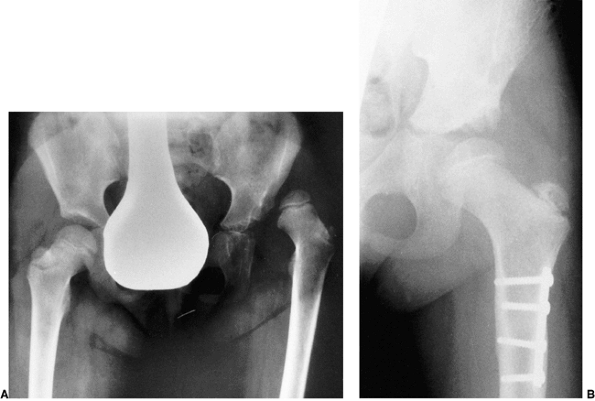

![]() |

Figure 24.28 A 5-month-old child with left developmental dislocation of the hip. A:

Anteroposterior view of the pelvis at diagnosis. The acetabular index is increased, the medial floor of the acetabulum is widened, and the acetabular teardrop figure is absent. There is a well-developed secondary acetabulum, the Shenton line is disrupted, and the femoral ossific nucleus is decreased in size. The femoral head is located in the upper outer quadrant, as defined by Hilgenreiner and Perkins lines. B: Anteroposterior view of the pelvis with a hip Pavlik harness in place to demonstrate an excellent reduction. Note the hyperflexed position. C: Anteroposterior view of the pelvis at 9 months of age shows reduction, early appearance of the teardrop figure, and improvement in the acetabular index. D: Anteroposterior view of the pelvis at 31 months of age. There is marked improvement in the acetabular teardrop figure and acetabular development. E: Anteroposterior view of the pelvis at 5 years of age. There has been continued improvement in acetabular and femoral head development. |